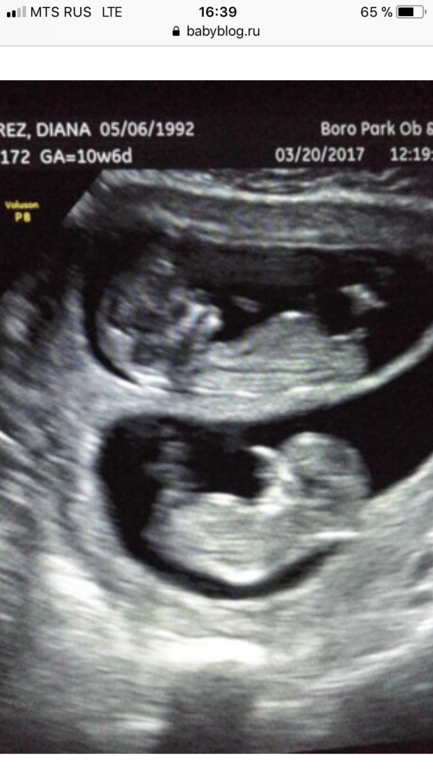

Спасибо большое за информацию) Мне так понравилось фото близнецов, где оба братики, и ещё тонна таких фото в сети, что я уже ничего не понимаю про углы и наклоны) Одно греет душу, что все параметры в норме, а фото чудесно) Вот эти братики)))